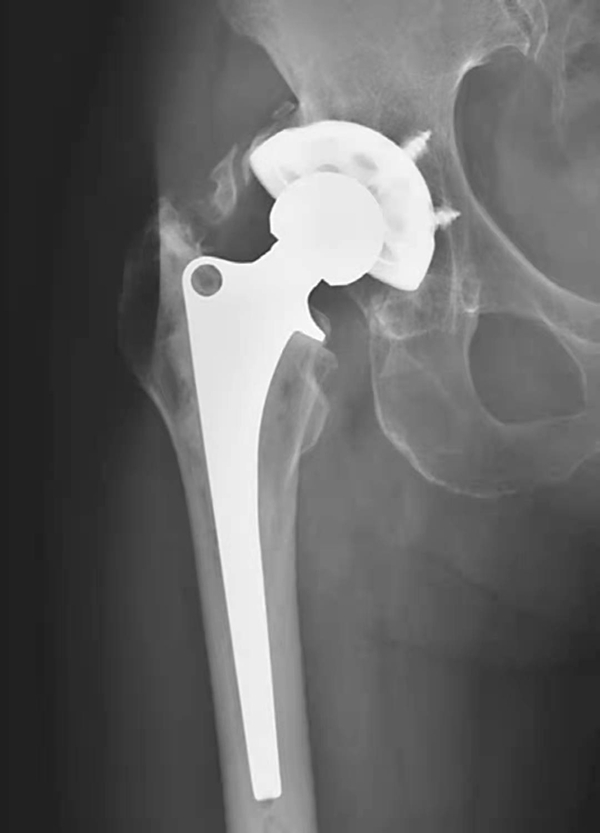

图4 右侧人工髋关节置换术后感染并松动

女性,89岁。发现右大腿中段后侧流脓2个月余。平片,示右股骨上段骨密度增高,内侧骨膜增生,假体周围骨质吸收,髋臼杯内陷,人工股骨柄部内移